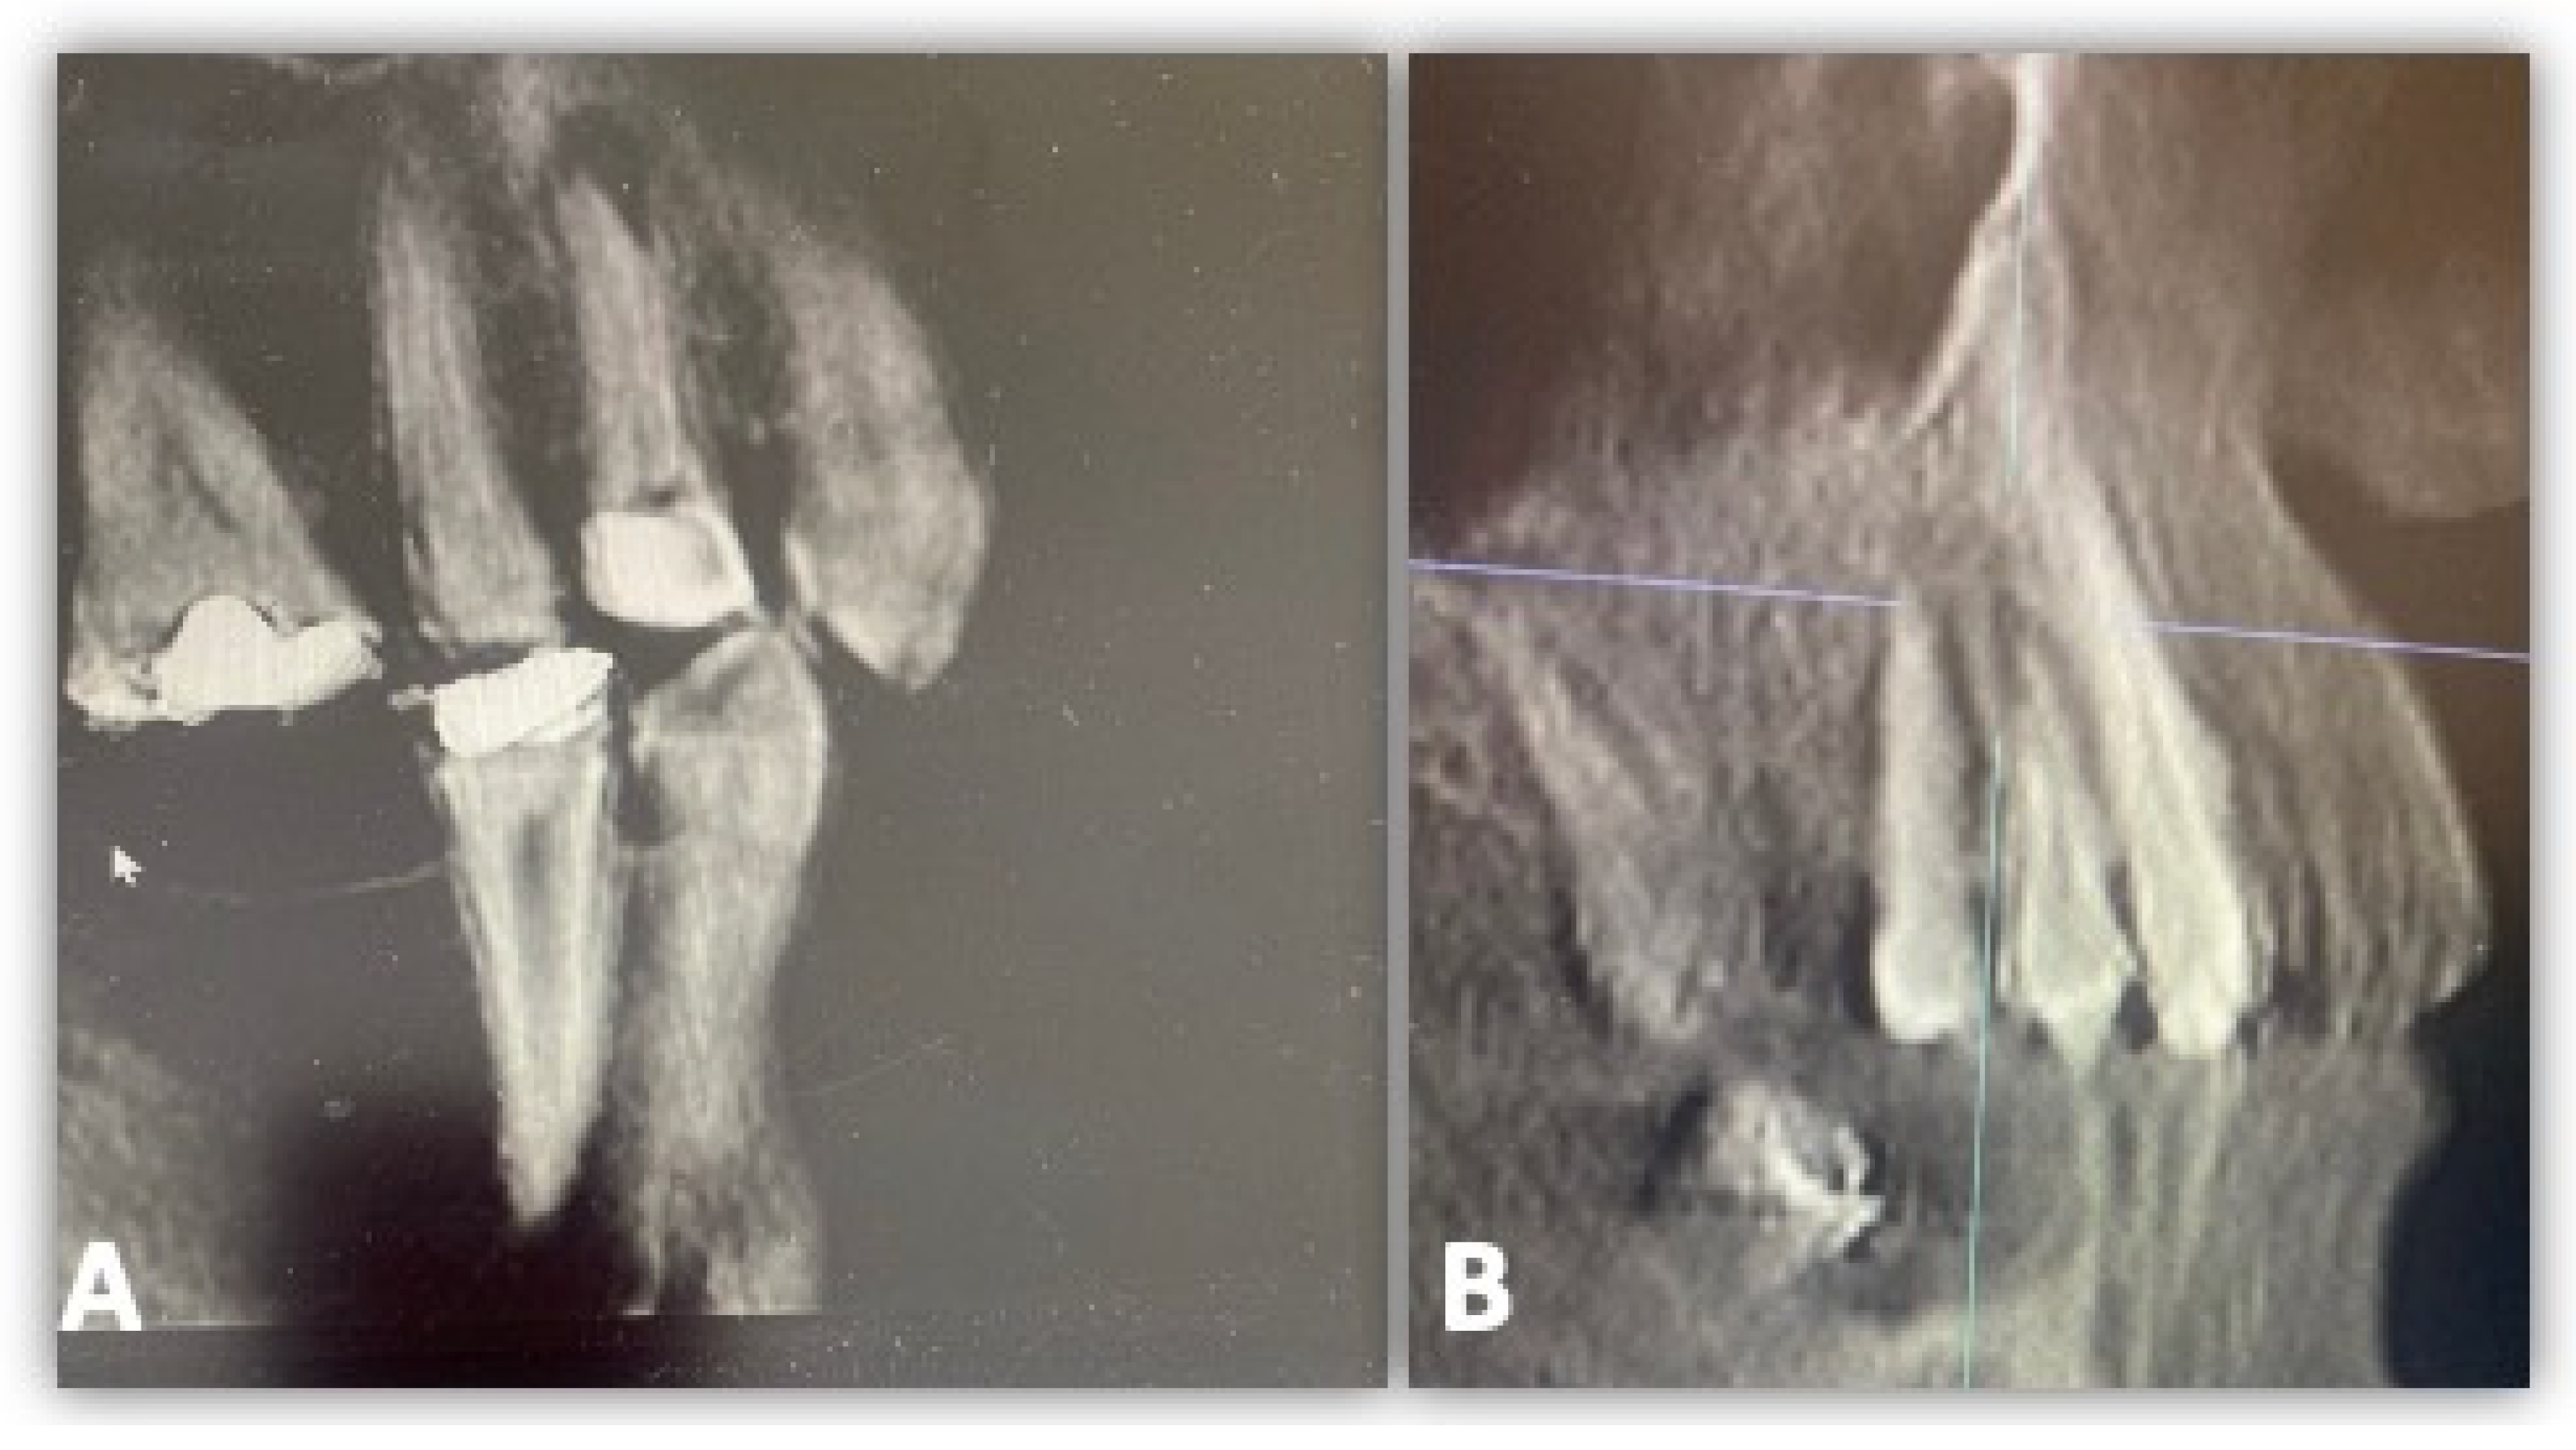

2.3. Study Criteria

2.4. GCF Samples Collection and Analysis